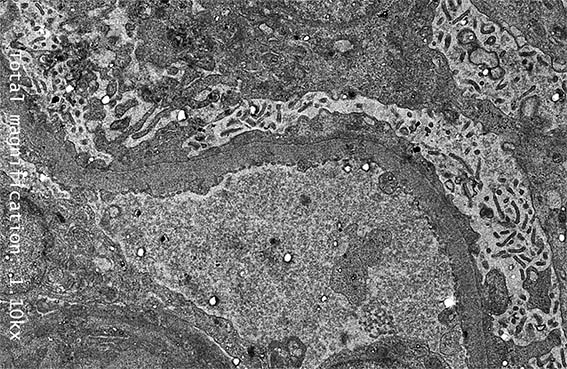

Figure 10. Diffuse podocyte damage, with microvillous transformation of the podocyte cytoplasm. EM, original magnification, X2,100.

Figure 11. EM, original magnification, X2,100.